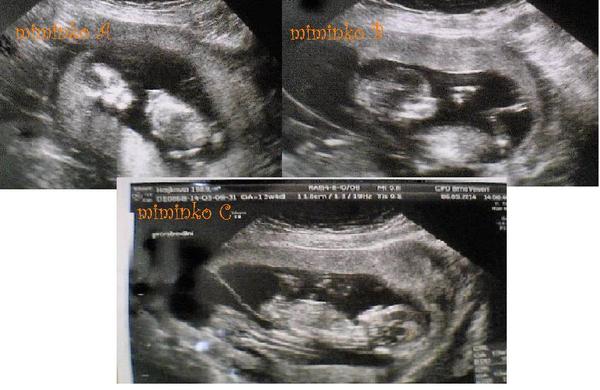

Tak děvčata trojčátka jsou vpořádku, všechny pěkně rostou.Segra to zatím zvládá obstojně.Teď jsou 15 tt.